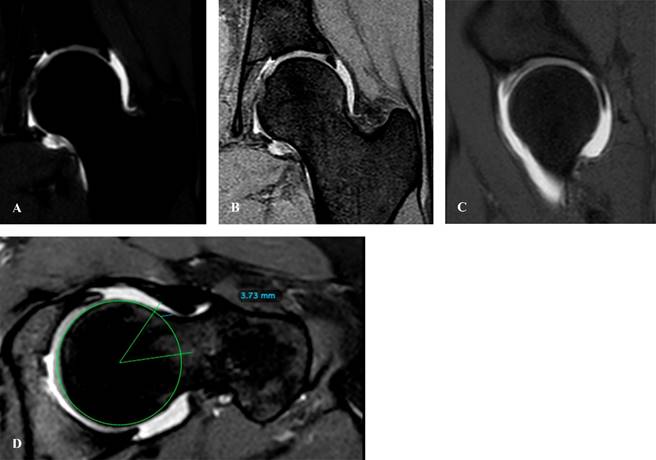

Resonancia magnética (RM)

De acuerdo con los criterios de imagen del Colegio Americano de Radiología Musculoesquelética, la resonancia magnética es el estudio estándar de oro para la evaluación de la cadera dolorosa en pacientes sin hallazgos anormales o patológicos en imagen radiológica. Para el abordaje de dolor no especificado o extraarticular, la resonancia simple es el estudio indicado; sin embargo, si la sintomatología es sugestiva de patología intraarticular, la artroresonancia de cortes finos (FOV [field of view]) es el estudio con mayor sensibilidad para dicho abordaje de valoración.16

El uso de artroresonancia ha revolucionado el diagnóstico de patología labrales y de cápsula, pudiendo comparar este estudio con los hallazgos artroscópicos. Se reporta una sensibilidad de 71%, especificidad de 44% y valor predictivo de 93% (Figura 12).17

Figura 12: A) Corte coronal en T1 de artroresonancia de cadera, se observa labrum anterosuperior. B) Misma lesión en secuencia T2 con supresión de grasa. C) Corte sagital en T1. D) Corte axial en secuencia T2, donde se realiza medición de ángulo alfa, con presencia de deformidad tipo cam de 3.7 mm.

No obstante, la resonancia de alta definición está llegando a sustituir este estudio de imagen más invasivo.16

Además del abordaje de patología intraarticular (Figura 13A), la resonancia magnética es de utilidad al identificar fracturas por estrés o fracturas patológicas (Figura 13B) cuya imagen no es claramente definida en estudio radiográfico simple. Se considera en estudio con mayor sensibilidad para la evaluación y diagnóstica de osteonecrosis (Figura 13C) y fractura por estrés.16,18